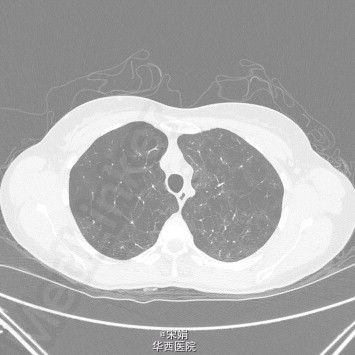

28岁的COPD,你遇到过吗?

COPD一般很少在年轻人中发生,几乎不在40岁以下的人群中诊断。此患者是 一个28岁的年轻女性,咳嗽、呼吸困难进行性加重2-3年,伴喘息、胸闷、夜间咳嗽,活动耐量低(MRC4分)。12年吸烟史,每天20支(!!),有甲减病史。家族中母亲和外婆都有COPD。治疗方面很遗憾,患者发病后仍持续吸烟,治疗效果不明显。